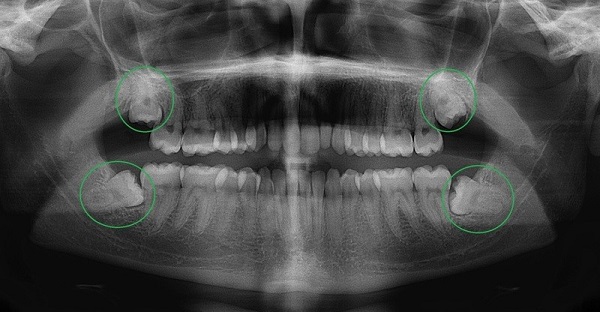

Chụp X quang toàn cảnh răng (chụp Panorama răng)

Đây là phương pháp chụp X quang được sử dụng để kiểm tra toàn bộ khoang miệng. Bằng cách sử dụng kỹ thuật chụp cắt lớp vi tính, nha sĩ có thể thấy rõ răng và mô xương. Trong quá trình chụp, bệnh nhân sẽ được bảo vệ bằng áo chì và cố định trên máy để thu được hình ảnh sắc nét của răng và xương hàm dưới.

Hình ảnh Panorama răng là một công nghệ chụp X quang cho thấy rõ về xương hàm trên và dưới, các thành phần lân cận như khớp thái dương hàm, xoang mũi. Kỹ thuật này cũng cho phép bác sĩ nhìn thấy toàn bộ hai cung răng trên một phim giúp chẩn đoán nhiều loại bệnh lý răng miệng như răng mọc lệch, răng mọc ngầm, u nang, áp xe và tổn thương xương hàm.

Ưu điểm của kỹ thuật Panorama răng là thời gian chụp nhanh, hình ảnh chất lượng cao, an toàn và phù hợp với mọi đối tượng, bao gồm cả trẻ em – nhóm khách hàng khó chụp X quang bằng các phương pháp truyền thống. Tuy nhiên, điểm trừ của phương pháp này là không phát hiện được những vấn đề như lỗ sâu răng, gãy xương, nhiễm trùng,…